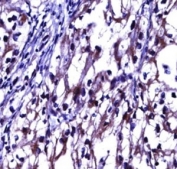

OPG antibody immunohistochemistry analysis in formalin fixed and paraffin embedded human kidney carcinoma.